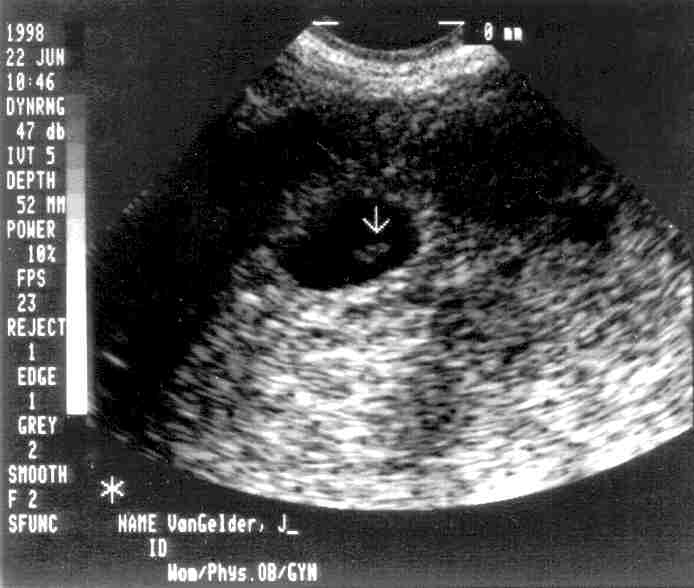

Peanut at 6 weeks

The dark area surrounding the arrow is the amniotic sac. The slightly lighter area under the arrow is the peanut. The dot in the middle is the heart, and it was beating! Peanut is about 1/2" long.